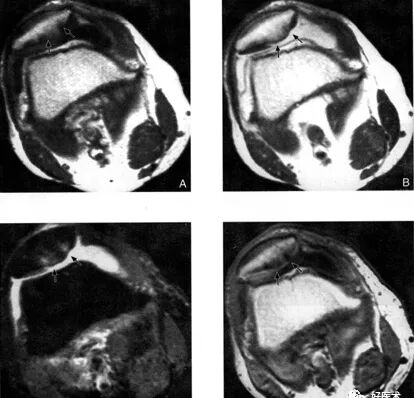

髌骨软骨软化症MRI表现:

0级:

A:SE序列T1加权像

B:SE序列T2加权像

C:STIR像

D:PGE序列T1加权像

Ⅱ级: